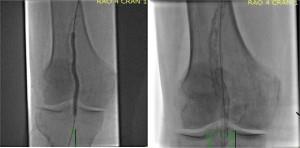

El retorcimiento poplíteo se teoriza como una de las causas de la falla del stent en el espacio poplíteo. En un interesante estudio de 68 pacientes sometidos a angiografía de la arteria poplítea, se identificó un punto de articulación en el 98,6% de los pacientes (Diaz et al. (1), ver figura 1).

Y

Imagen utilizada con permiso del Dr. Chris Metzger, Director de Cardiac and Peripheral Labs en Holston Valley, Kingsport Tennessee. Debido al movimiento intrínseco de la articulación de la rodilla y la generación de un punto de articulación, el uso de PTA solo, los stents autoexpansibles con propiedades de resistencia al aplastamiento y los injertos endovasculares de stent han sido ampliamente estudiados. La tasa promedio de permeabilidad de la arteria poplítea después de la PTA sola es aproximadamente del 47% a los 2 años. Cuanto mayor sea la longitud de la lesión, mayores serán las tasas de reestenosis. (referencia 1, referencia 2, referencia 3).